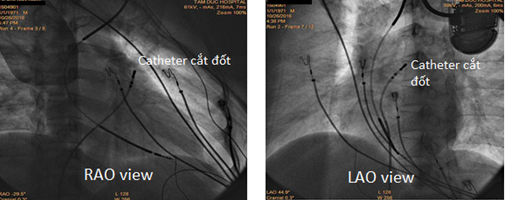

Lập bản đồ 3D xác định vị trí điện thế sớm nhất của ngoại tâm thu nằm ở vùng trước vách của buồng tống thất phải (47ms trước phức bộ ngoại tâm thu). Tiến hành cắt đốt tại vị trí này bằng năng lượng sóng cao tần (40W, 60oC). Sau cắt đốt không còn ngoại tâm thu thất. Theo dõi sau cắt đốt 6 tháng, bệnh nhân hoàn toàn không triệu chứng sau khi ngưng tất cả các thuốc chống loạn nhịp. Kiểm tra máy ICD không có ghi nhận cơn loạn nhịp thất nào.

Hình 7. Hình ảnh dựng hình 3D cấu trúc buồng tống thất phải và bản đồ điện thế xác định vị trí ổ ngoại vị.

Hình 8. Hình ảnh trên màn huỳnh quang cho thấy vị trí catheter cắt đốt phần trước vùng vách của buồng tống thất phải